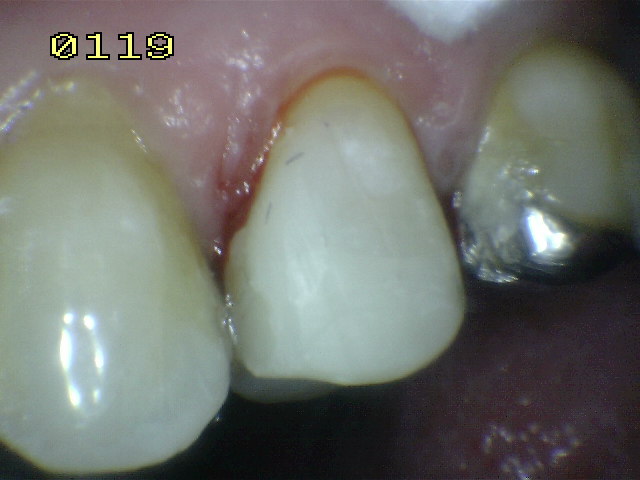

| También se

baja la cúspide vestibular o de corte , para prevenir

una fractura dental.. |

Se coloca

una matriz circular, se acuña y se bruñen los puntos de

contacto y por ultimo se graba con acido durante 30

segundos. |

Se seca

por 30 segundos, se aplica el agente de enlace y se

activa con luz halógena por 20 segundos. La resina

compuesta flow es aplicada en la caja mesial y

distal para fijar la matriz, una vez polimerizada. |